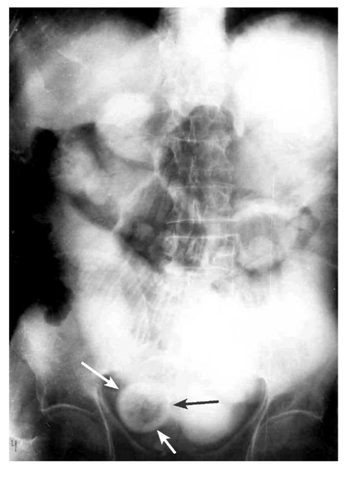

בצילום בטן סקירה ניתן לראות חסימות דינמיות, התרחבות של המעי הדק (תצלום 1.4), ופלסי אוויר נוזל במרכז הבטן המסודרים בצורת מדרגות (תצלום 2.4). הוולבולה קוניובנטס מודגשים לרוחב הרירית (תצלום 3.4).

בחסימות של המעי הדק לא תהיה עדות לאוויר בכרכשת (תצלום 4.4 - 5.4). בצילום צדדי של החלחולת לא ניתן לראות אוויר בחלחולת. לעומת זאת, בחסימות של הכרכשת יש הרחבה של הכרכשת והדגשה של ההאוסטרות בהיקף הבטן. בחולים שאובחנה בהם חסימה של הכרכשת, שבהם מסתם אילאוצקלי בלתי פעיל, תיראה הרחבה של הכרכשת והמעי הדק.